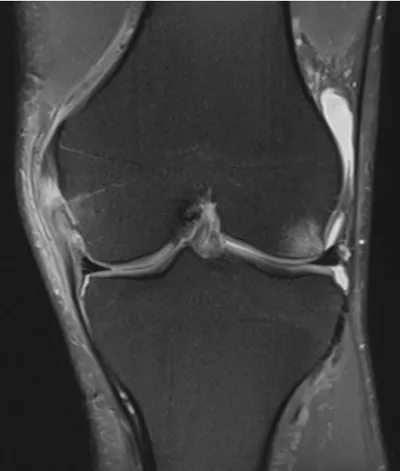

Grade 1 MCL injury

MRIKneeCoronal+1

4/23/2026